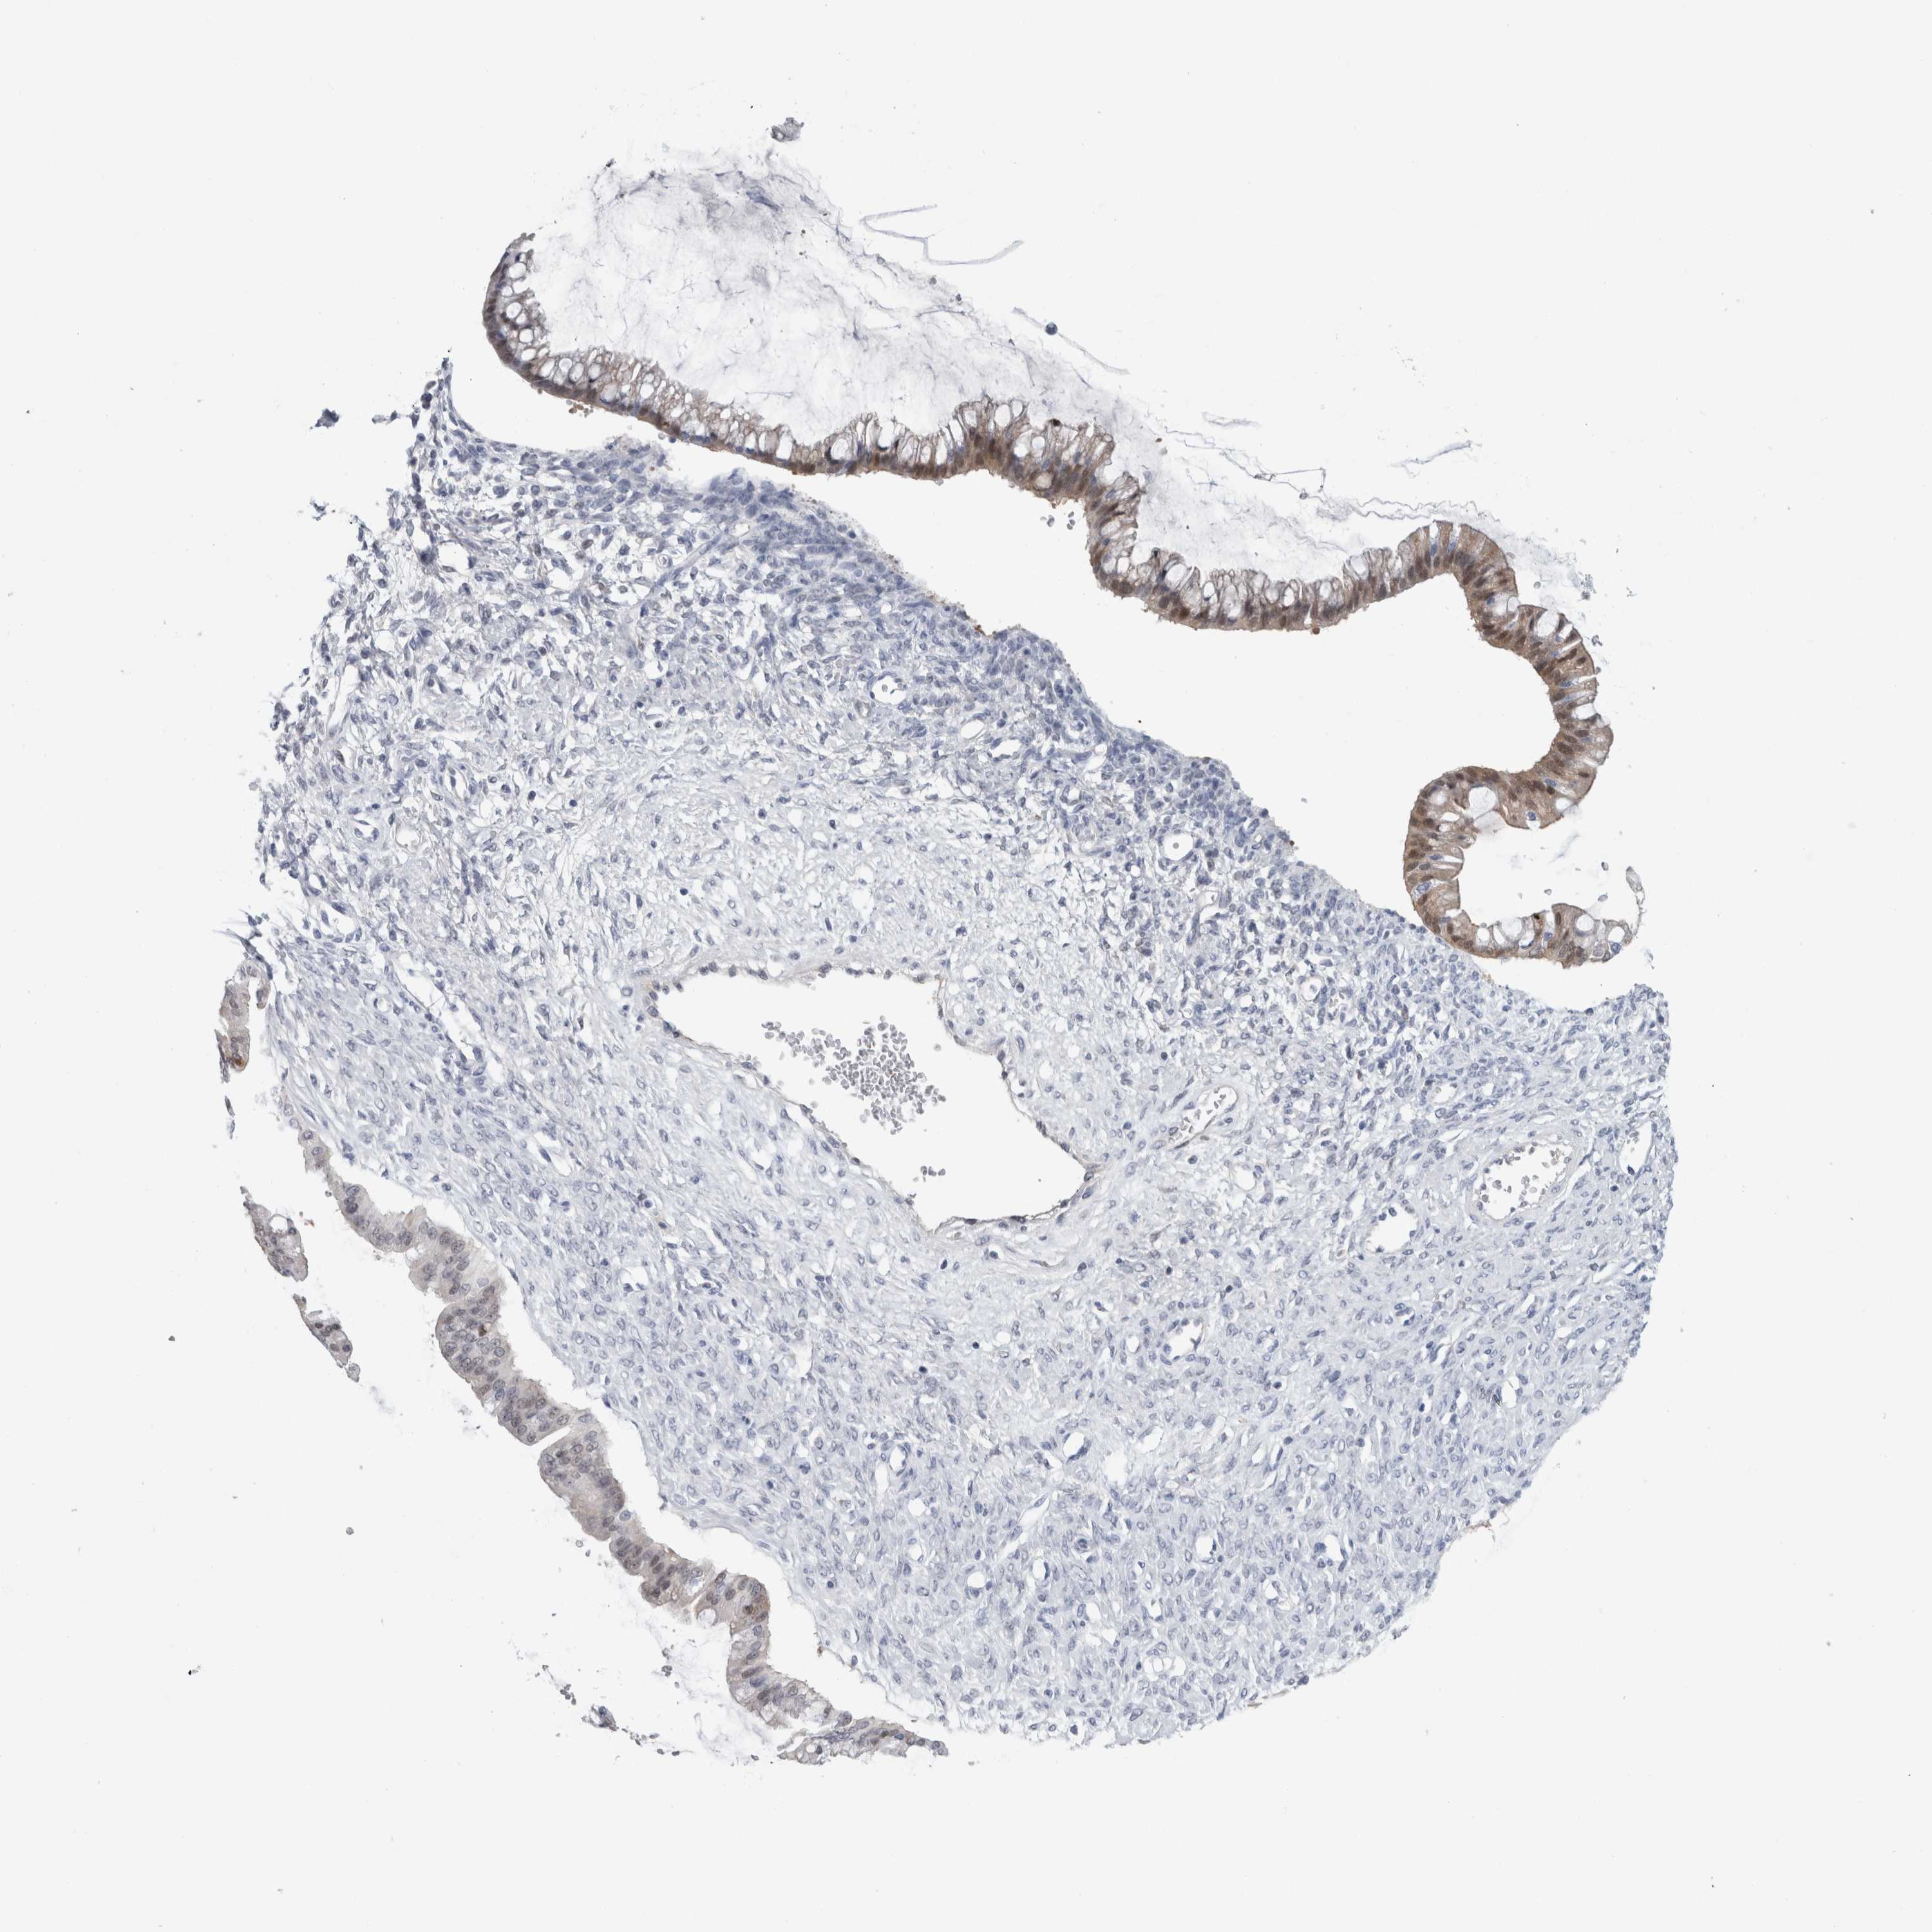

OVARIAN CANCER - Protein expressioni

A mouse-over function shows sample information and annotation data. Click on an image to view it in a full screen mode. Samples can be filtered based on level of antibody staining by selecting one or several of the following categories: high, medium, low and not detected. The assay and annotation is described here.

Note that samples used for immunohistochemistry by the Human Protein Atlas do not correspond to samples in the TCGA dataset.

Antibody stainingi

Antibody staining in the annotated cell types in the current human tissue is reported as not detected, low, medium, or high, based on conventional immunohistochemistry profiling in selected tissues. This score is based on the combination of the staining intensity and fraction of stained cells.

Each image is clickable and will lead to virtual microscopy that enables deeper exploration of all samples and also displays staining intensity scores, fraction scores and subcellular localization as well as patient and tissue information for each sample.

Antibody HPA011337

Antibody HPA024303

Antibody CAB003775

Carcinoma, NOS

Cystadenocarcinoma, serous, NOS